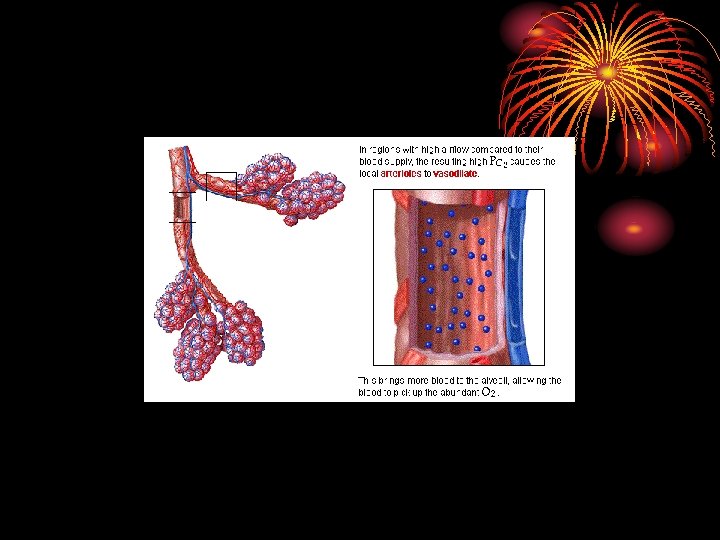

Ventilation-perfusion ratio V/Q • Pulm. alveolar ventilation / perfusion = 4. 2/5. 5 = 0. 8. • Both ventilation and perfusion decreases towards the apex, but the perfusion decreases more, so V/Q increases at the apex (more PO 2 T. B) at apex.